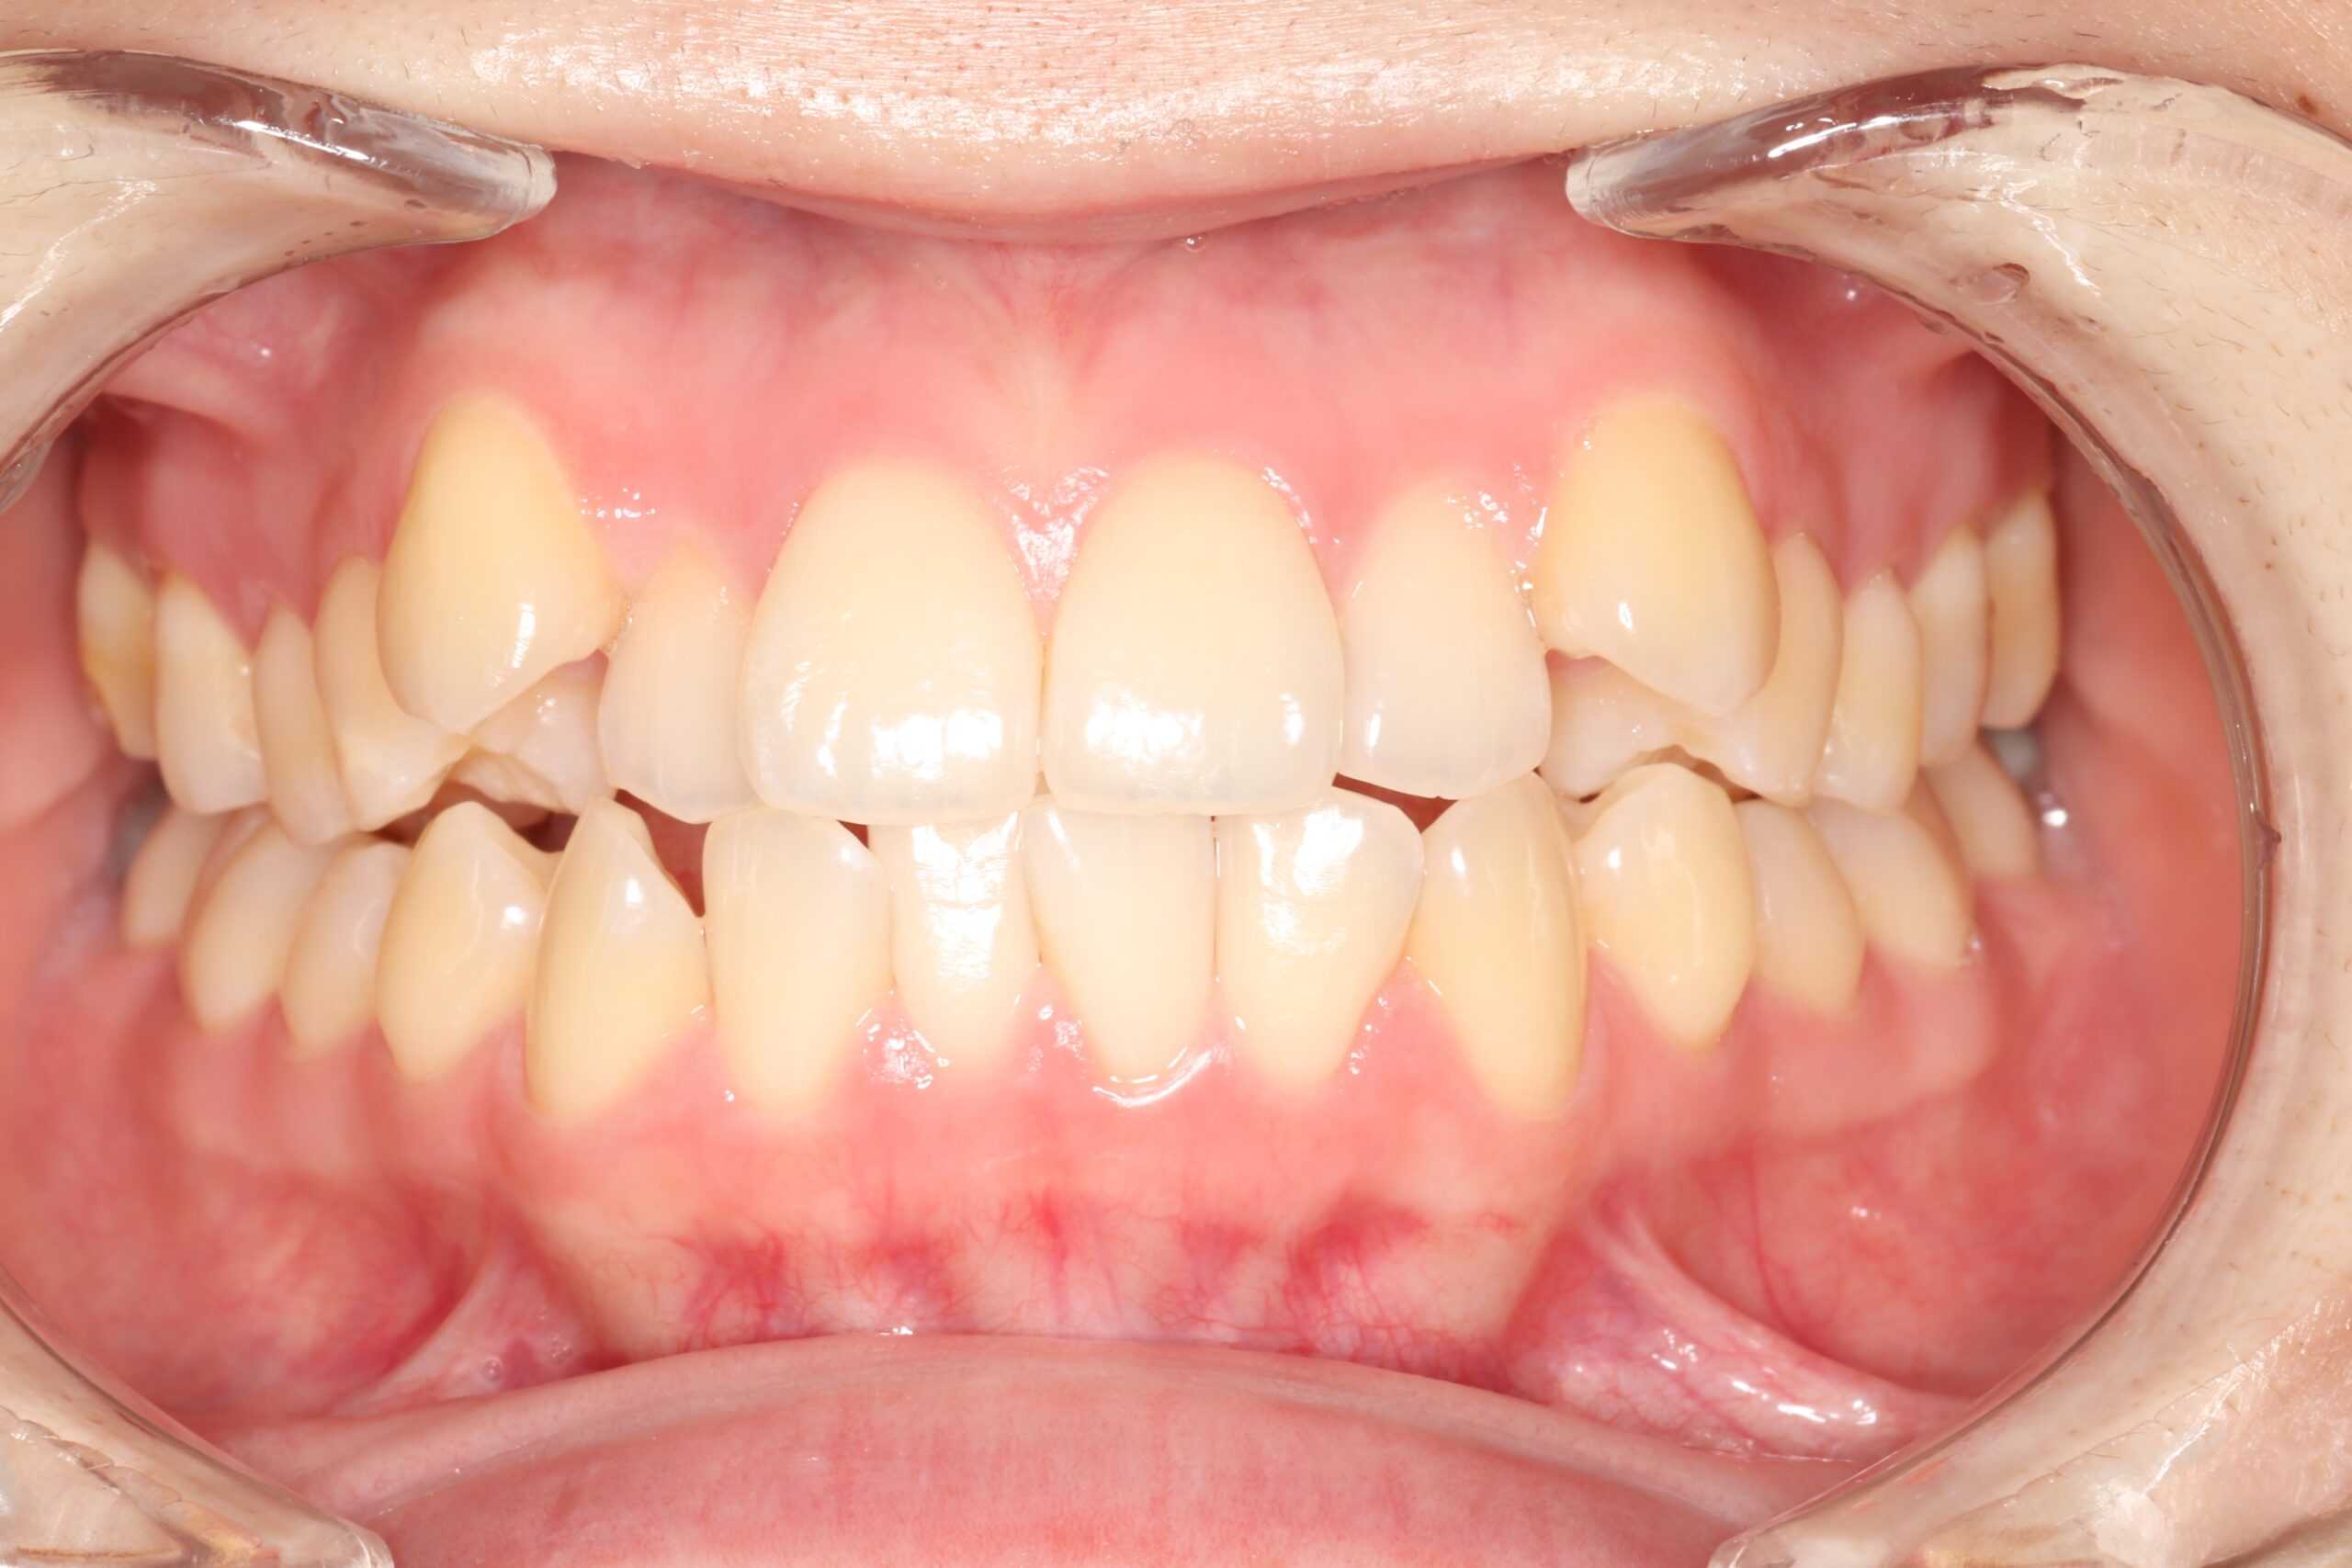

歯と歯の間に隙間がある状態です。

食事のときにうまく噛みきれなかったり、食べ物が歯に詰まりやすくなるなどのデメリットの他に、歯と歯の間から空気が抜けることで、発音にも支障が出るケースもあります。